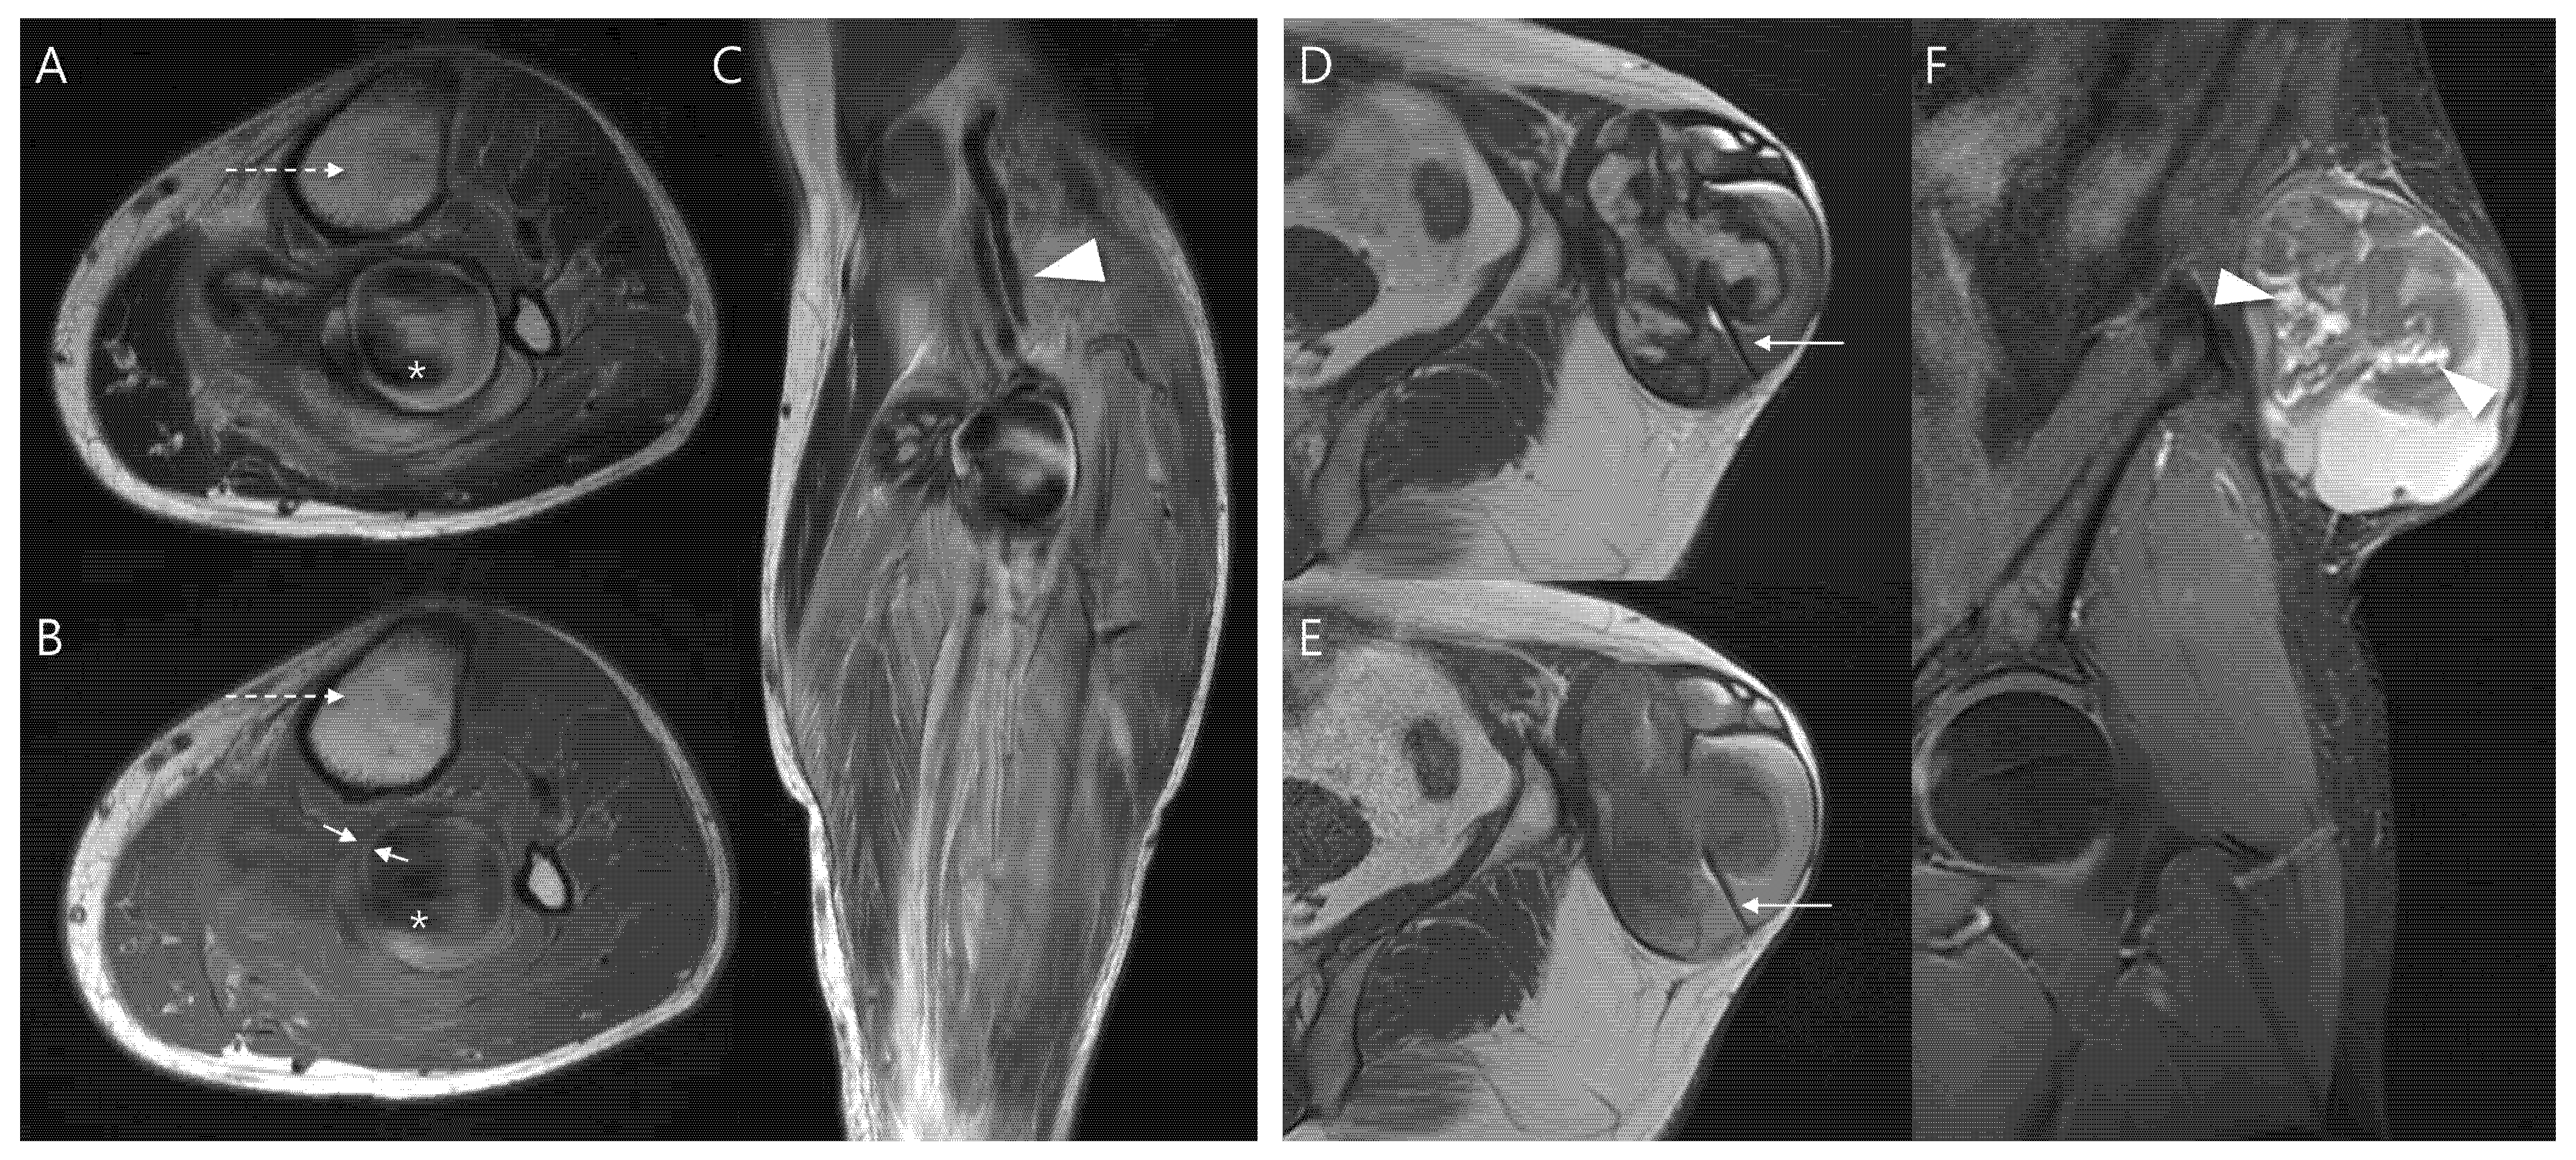

Using the proposed diagnostic flowchart, we successfully applied this approach in representative cases. In a representative pseudoaneurysm case (Figure 3), the hematoma-like lesion demonstrated a central flow void with adjacent neurovascular bundle involvement on MRI, which allowed a confident diagnosis of pseudoaneurysm; the patient subsequently underwent successful endovascular embolization. In contrast, in a CEH case (Figure 4), the lesion exhibited a multilobular hematoma-like lesion with internal septations and lacked neurovascular bundle involvement, findings that favored the diagnosis of CEH and were later confirmed after wide surgical excision. These representative cases underscore the practical utility of the flowchart by illustrating how specific imaging features can be translated into accurate diagnostic decisions and directly guide appropriate therapeutic strategies.

Figure 3.

Diagnosis and treatment of pseudoaneurysm. (A) Axial T2-weighted, T1-weighted, and coronal T1-weighted contrast-enhanced MR images show an intramuscular, ovoid lesions (arrow) in the upper arm. The lesion demonstrates a central flow void with inner peripheral high SI on T1-weighted image (arrow, mural thrombus) with neurovascular involvement (arrowhead). (B) Digital subtraction angiography reveals a pseudoaneurysm sac (arrow) with a narrow neck arising from the brachial artery (arrowhead). (C) Post-embolization angiography demonstrates successful occlusion of the pseudoaneurysm neck (arrowhead).

Figure 4.

Diagnosis and treatment of chronic expanding hematoma. (A) Sagittal and axial T2-weighted MR images demonstrate a multilobular, subcutaneous mass (thick arrows) with internal septations. The lesion shows peripheral nodular enhancement (thin arrows, granulation tissue) on coronal T1-weighted contrast-enhanced MR image. (B) Ultrasound-guided biopsy was performed using a core needle (arrows), confirming the hematoma. (C) Gross photograph of the wide excision demonstrates chronic expanding hematoma.